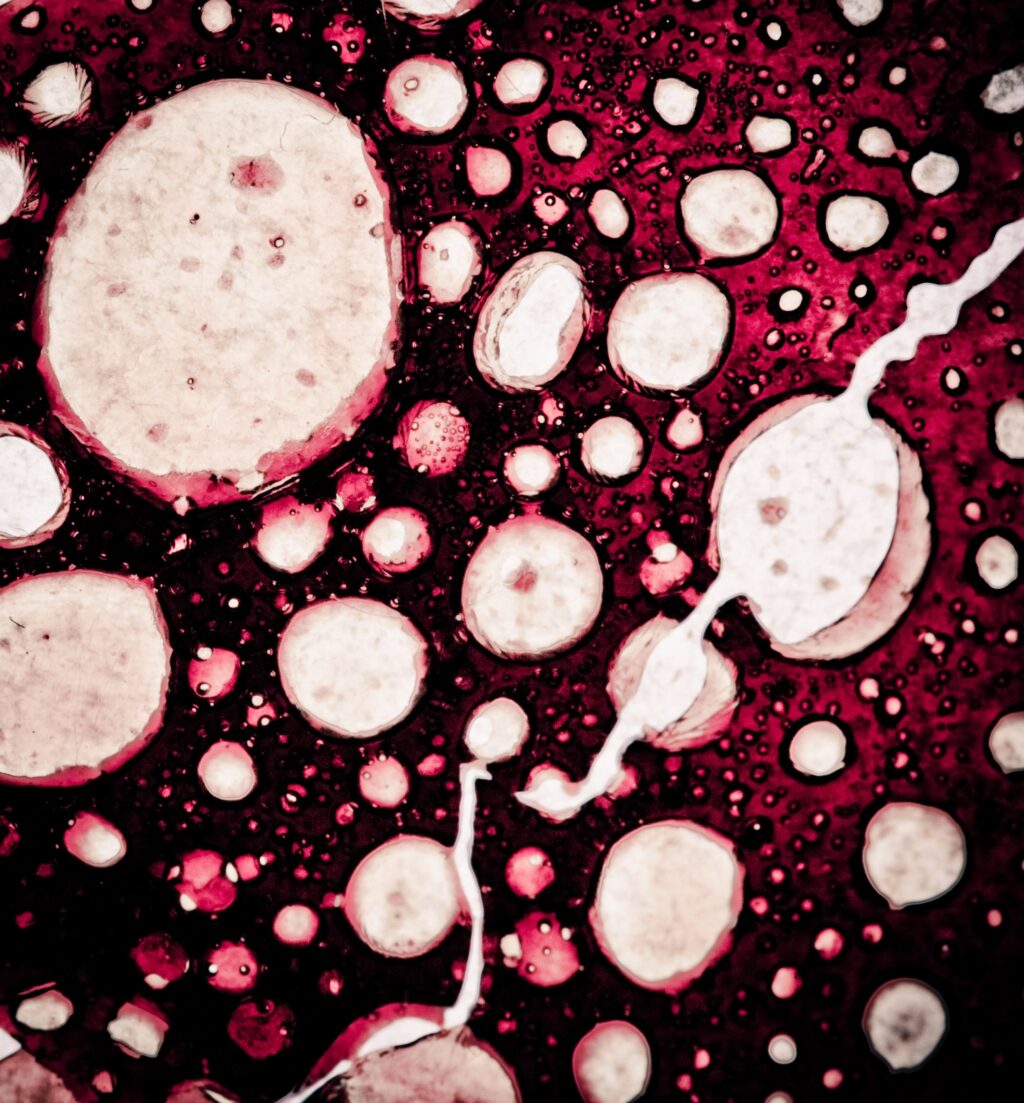

Celule canceroase / Foto: Shutterstock

Potrivit studiului, celulele canceroase pot „evita” acțiunea imunitară prin mecanismul metastazei, procesul prin care aceste celule se desprind de tumora primară și se regenerează în alte părți ale corpului, notează Hotnews.

Cercetătorii au analizat debutul precoce al metastazelor, iar ulterior au identificat în interiorul tumorilor prezența celulelor pre-metastatice, care se puteau deplasa în alte părți ale corpului, trecând prin ganglionii limfatici.